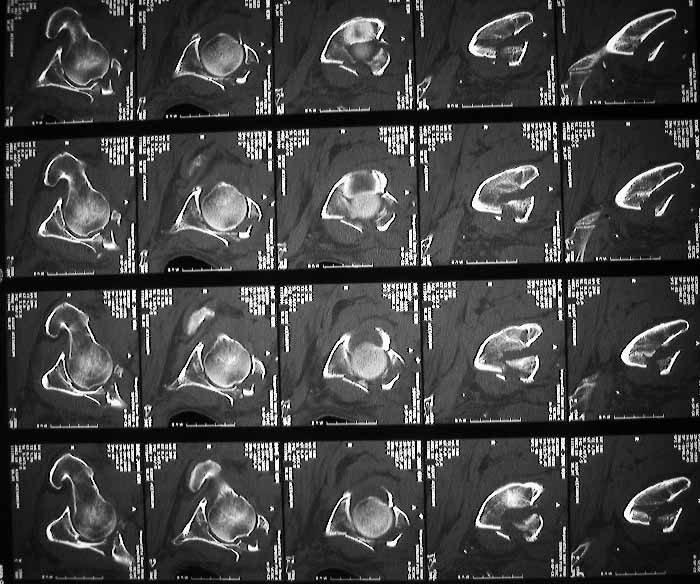

63 year old male, simple fall 4 days ago with an undisplaced Right Surgical neck of humerus fracture and this acetabular fracture. My assessment is that it is an anterior wall & column fracture with a blow out of the quadrilateral plate. the posterior column is intact. I see the immediate options as an attempted closed reduction and traction or an open reduction. I am right in saying this would need to be openly reduced through an ilioinguinal approach (which I have never seen or done). Or do I wait and do his Total Hip Replacement when his fracture has healed?

Next would be ORIF, via an ilioinguinal incision by an experienced surgical team. If you are unable, he should be referred appropriately, and could travel safely in traction via air or ground ambulance, depending upon distance.

Expected result of ORIF of this injury would be a durable, good hip joint, rarely requiring THA.